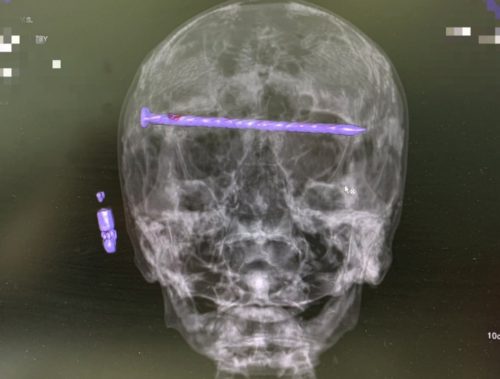

Сложная операция в Нижнем Тагиле: врачи удалили 15-сантиметровый гвоздь из головы пациента

78-летний мужчина успешно перенёс экстренную нейрохирургическую операцию.

Нижнетагильские врачи в результате сложнейшей операции достали из головы 78-летнего пациента 15-сантиметровый гвоздь.

Мужчина поступил в приёмный покой Городской больницы №1 Нижнего Тагила в тяжёлом состоянии. На КТ медики увидели в костях черепа гвоздь, который прошёл через обе глазницы от правого до левого виска. Длина его достигала 15 сантиметров. Ситуация осложнялась повреждением твёрдой оболочки мозга и сдавлением глазных яблок.

Чтобы спасти пациента, бригада специалистов во главе с заведующим нейрохирургическим отделением ГБ №1 Нижнего Тагила Дмитрием Неволиным провела экстренную операцию. Гвоздь извлекли, сохранив мужчине и жизнь, и зрение.

Прооперированный мужчина под наблюдением бригады врачей быстро восстанавливается. Для профилактики осложнений он проходит антибактериальную терапию.